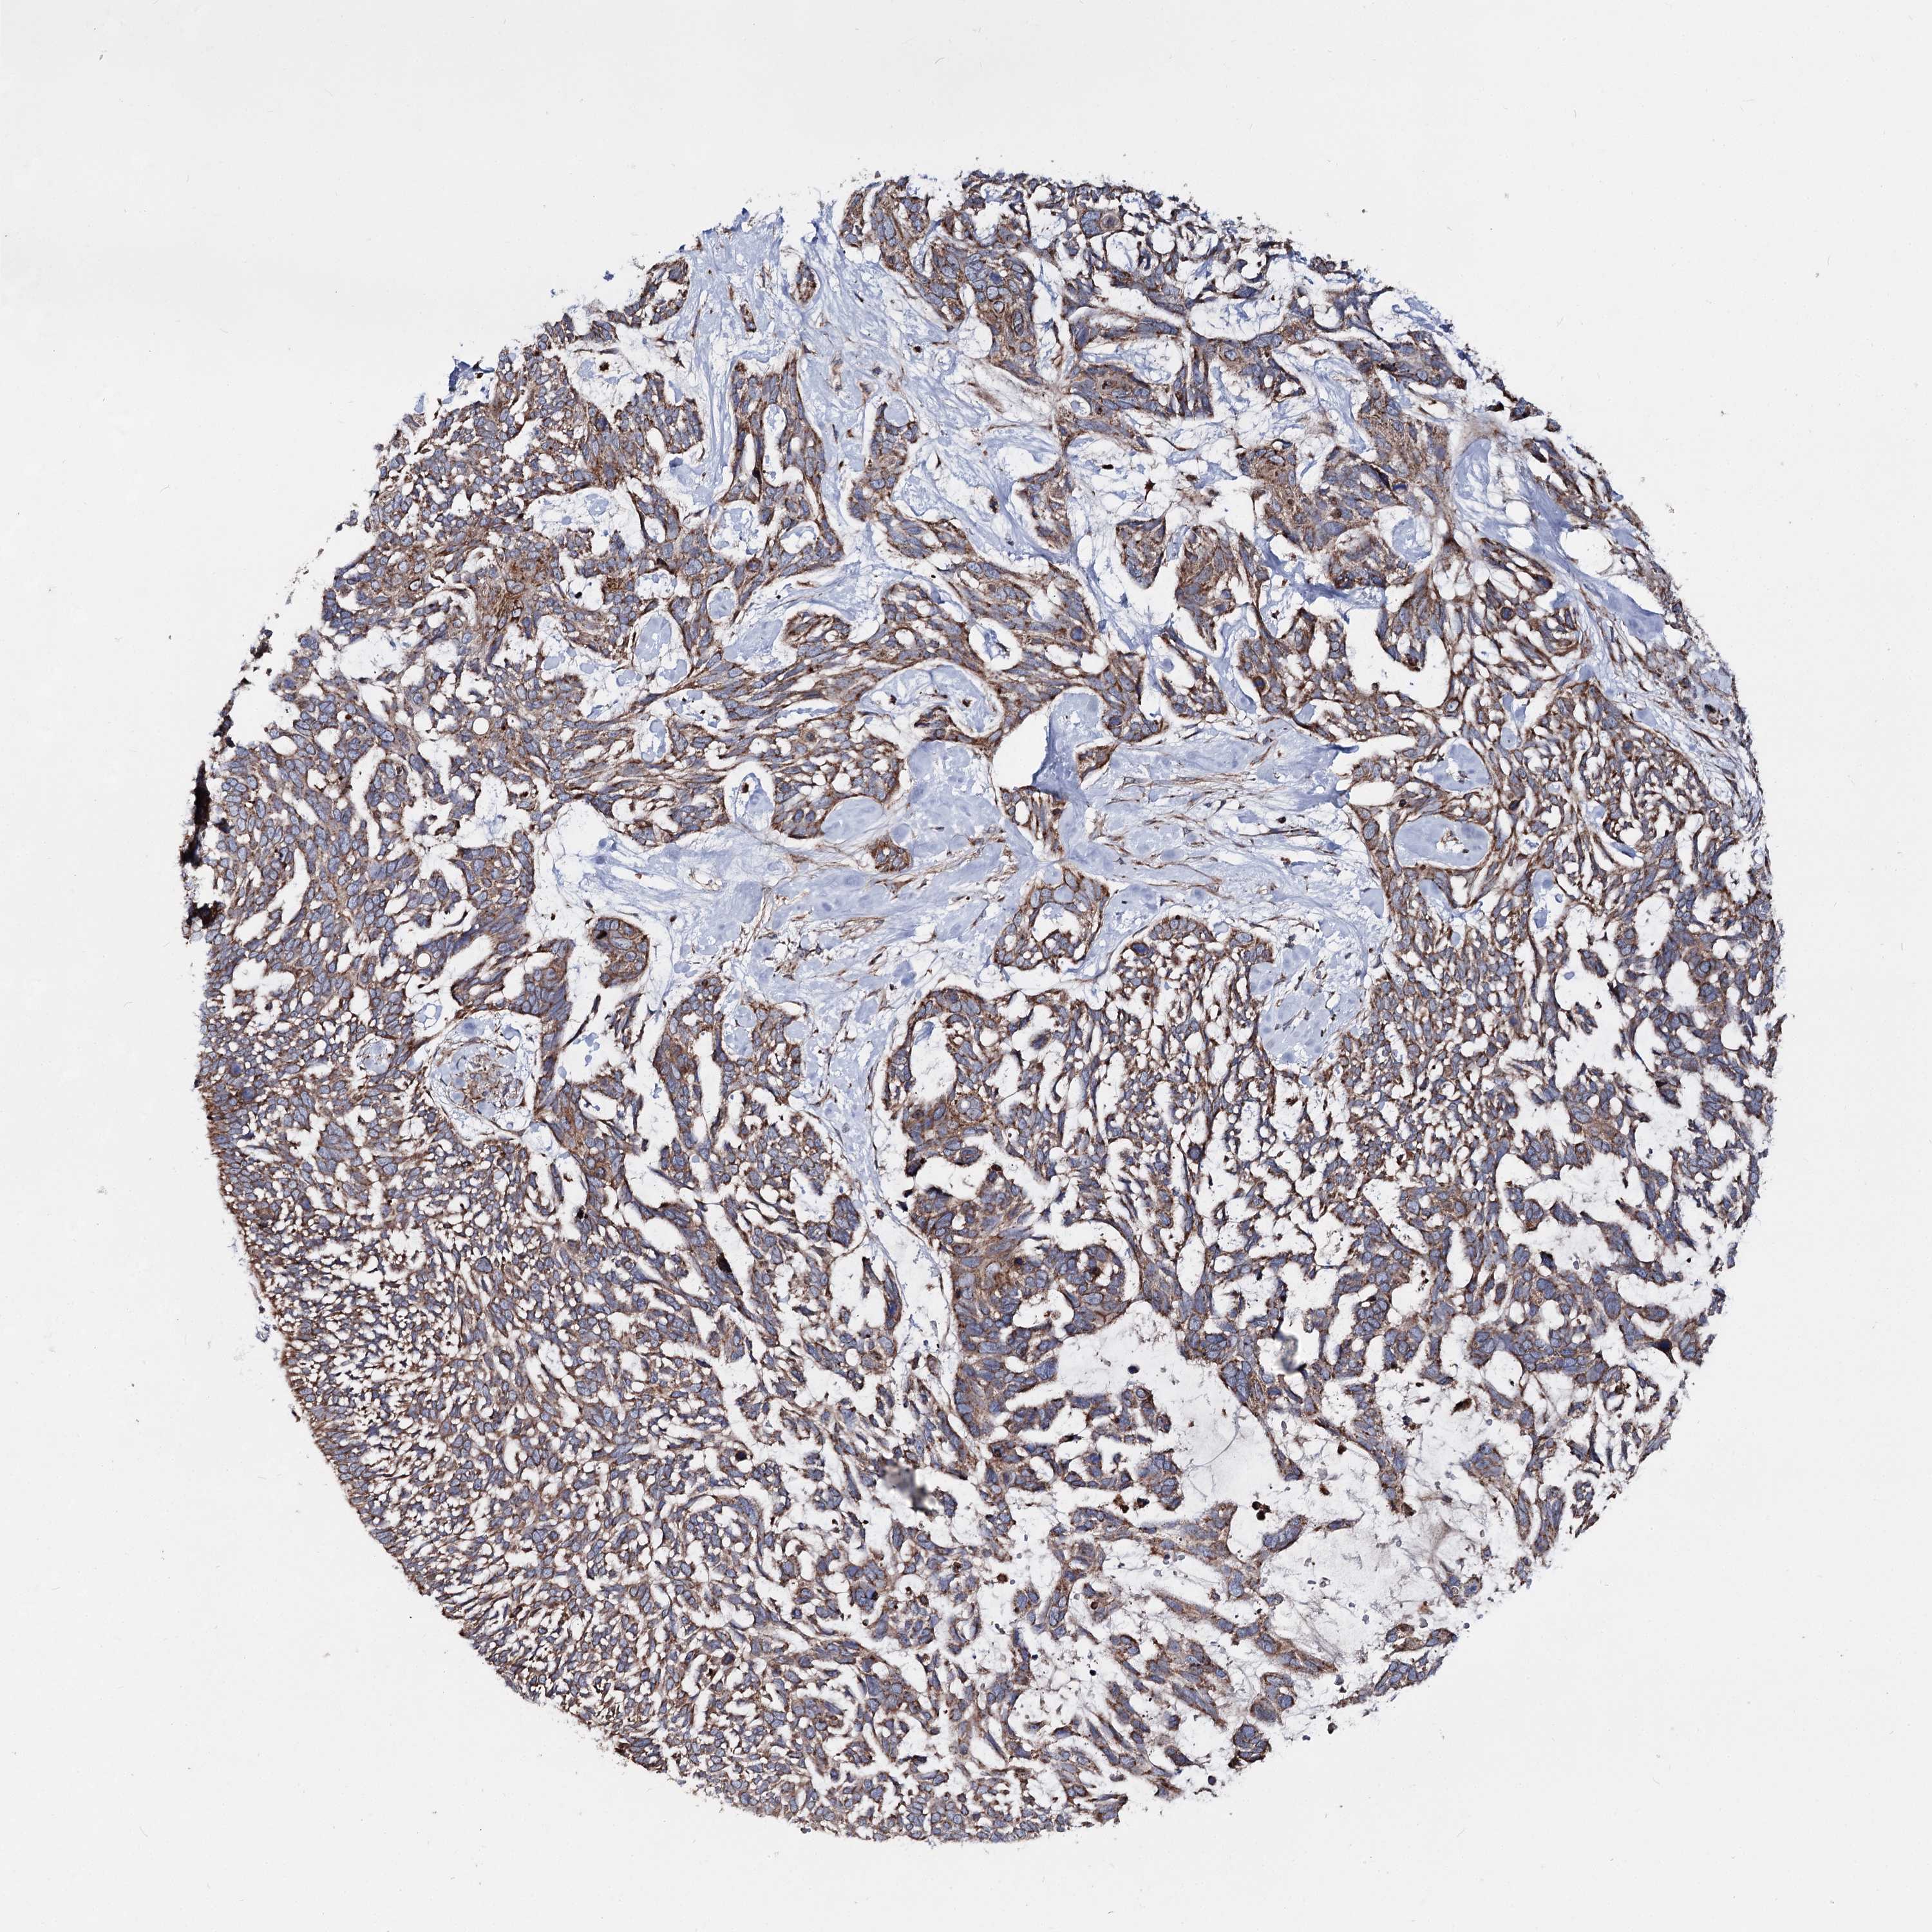

SKIN CANCER - Protein expressioni

A mouse-over function shows sample information and annotation data. Click on an image to view it in a full screen mode. Samples can be filtered based on level of antibody staining by selecting one or several of the following categories: high, medium, low and not detected. The assay and annotation is described here.

Antibody stainingi

Antibody staining in the annotated cell types in the current human tissue is reported as not detected, low, medium, or high, based on conventional immunohistochemistry profiling in selected tissues. This score is based on the combination of the staining intensity and fraction of stained cells.

Each image is clickable and will lead to virtual microscopy that enables deeper exploration of all samples and also displays staining intensity scores, fraction scores and subcellular localization as well as patient and tissue information for each sample.

Antibody HPA038695

Squamous cell carcinoma, NOS